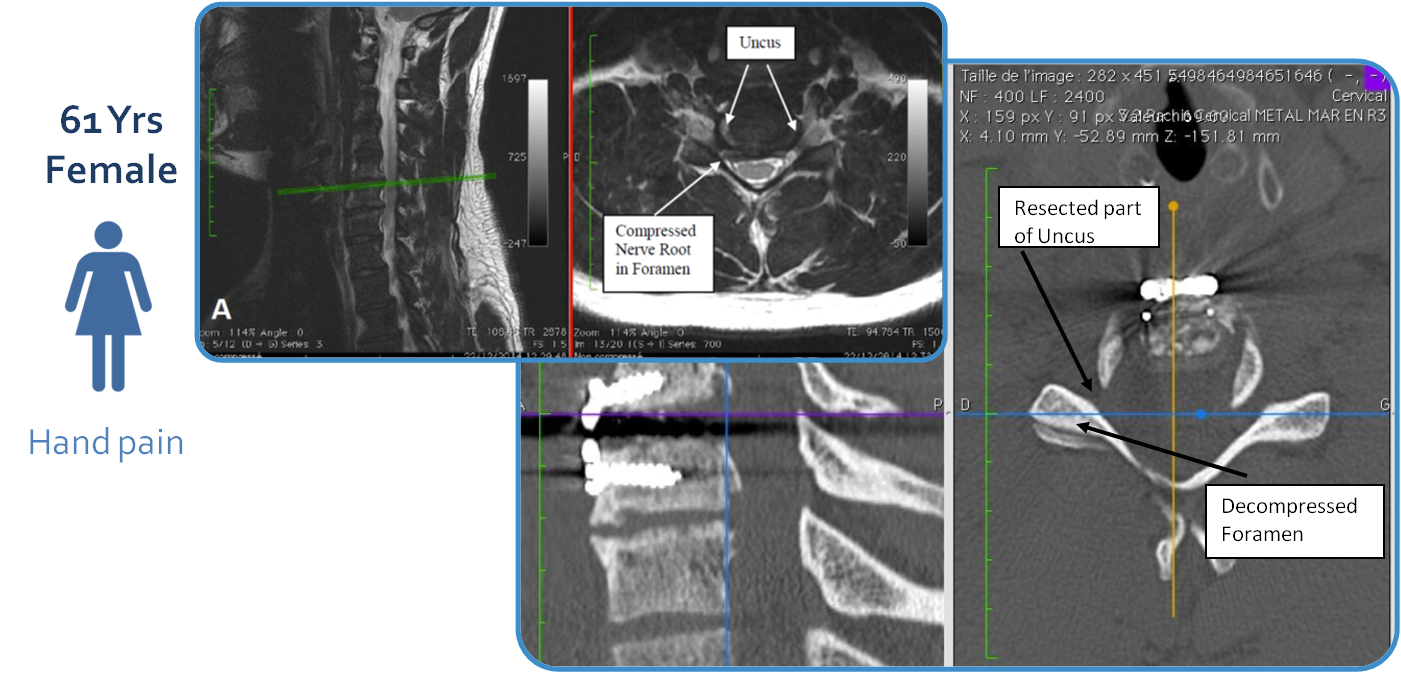

CASE #2 – Cervical- 61 year old female – severe hand pain